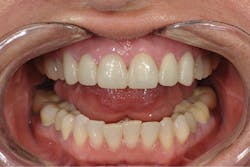

The enamel was selectively acid etched with Select HV Etch (Bisco). This is a 35% high-viscosity phosphoric acid etchant available with benzalkonium chloride, an antimicrobial agent that does not slump. The teeth were then treated with All-Bond Universal (Bisco), which is a light-cure bonding agent that is compatible with light, self and dual-cured cementation materials. The manufacturer’s instructions were followed.5 The eCement was then placed in the crowns and cured for 2 to 3 seconds only. The excess cement was removed, and the final cure was completed. The teeth were seated two at a time, starting with Nos. 8 and 9. After all crowns were seated, final cleanup was completed, occlusion was verified, and minor esthetic correction was completed (figures 7 and 8).

Figure 7: Anterior retracted view of the patient’s final restoration